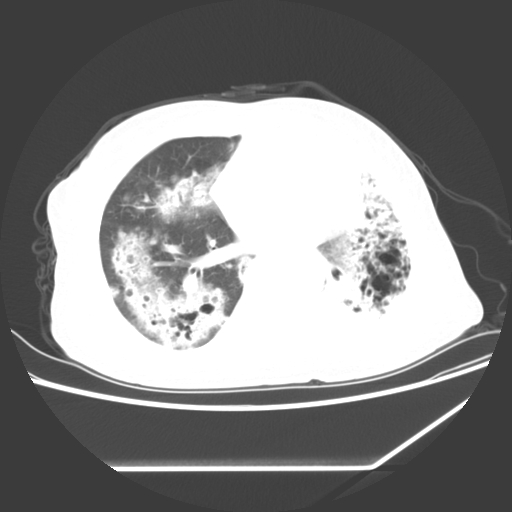

标题: CT25393:病人45岁,咳嗽,吐黄痰带血丝,发热,胸闷月余 [打印本页]

标题: CT25393:病人45岁,咳嗽,吐黄痰带血丝,发热,胸闷月余

1、左肺中央型肺癌并双肺弥漫性转移   2、双肺部感染    3、肺大泡     4、左侧胸腔积液

双侧肺弥漫性病变,可见“空泡征”及“蜂窝征”,考虑肺泡癌可能性大,左侧胸腔积液,考虑胸膜受累可能!

考虑肺泡癌,建议排除感染。

考虑肺泡癌

1)不排除肺泡癌可能。2)左侧胸腔积液。